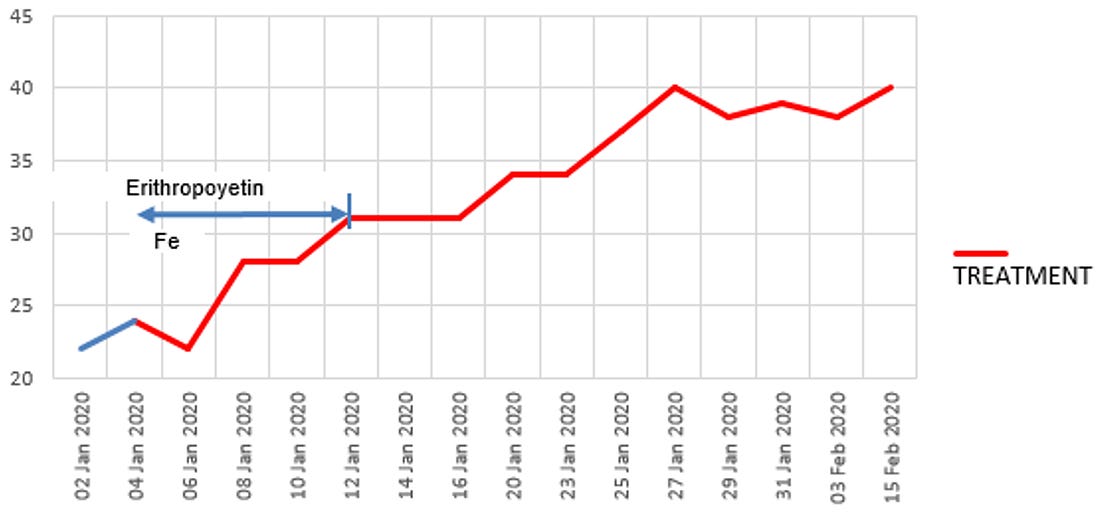

project involved treating approximately 85 patients, with the cure rate